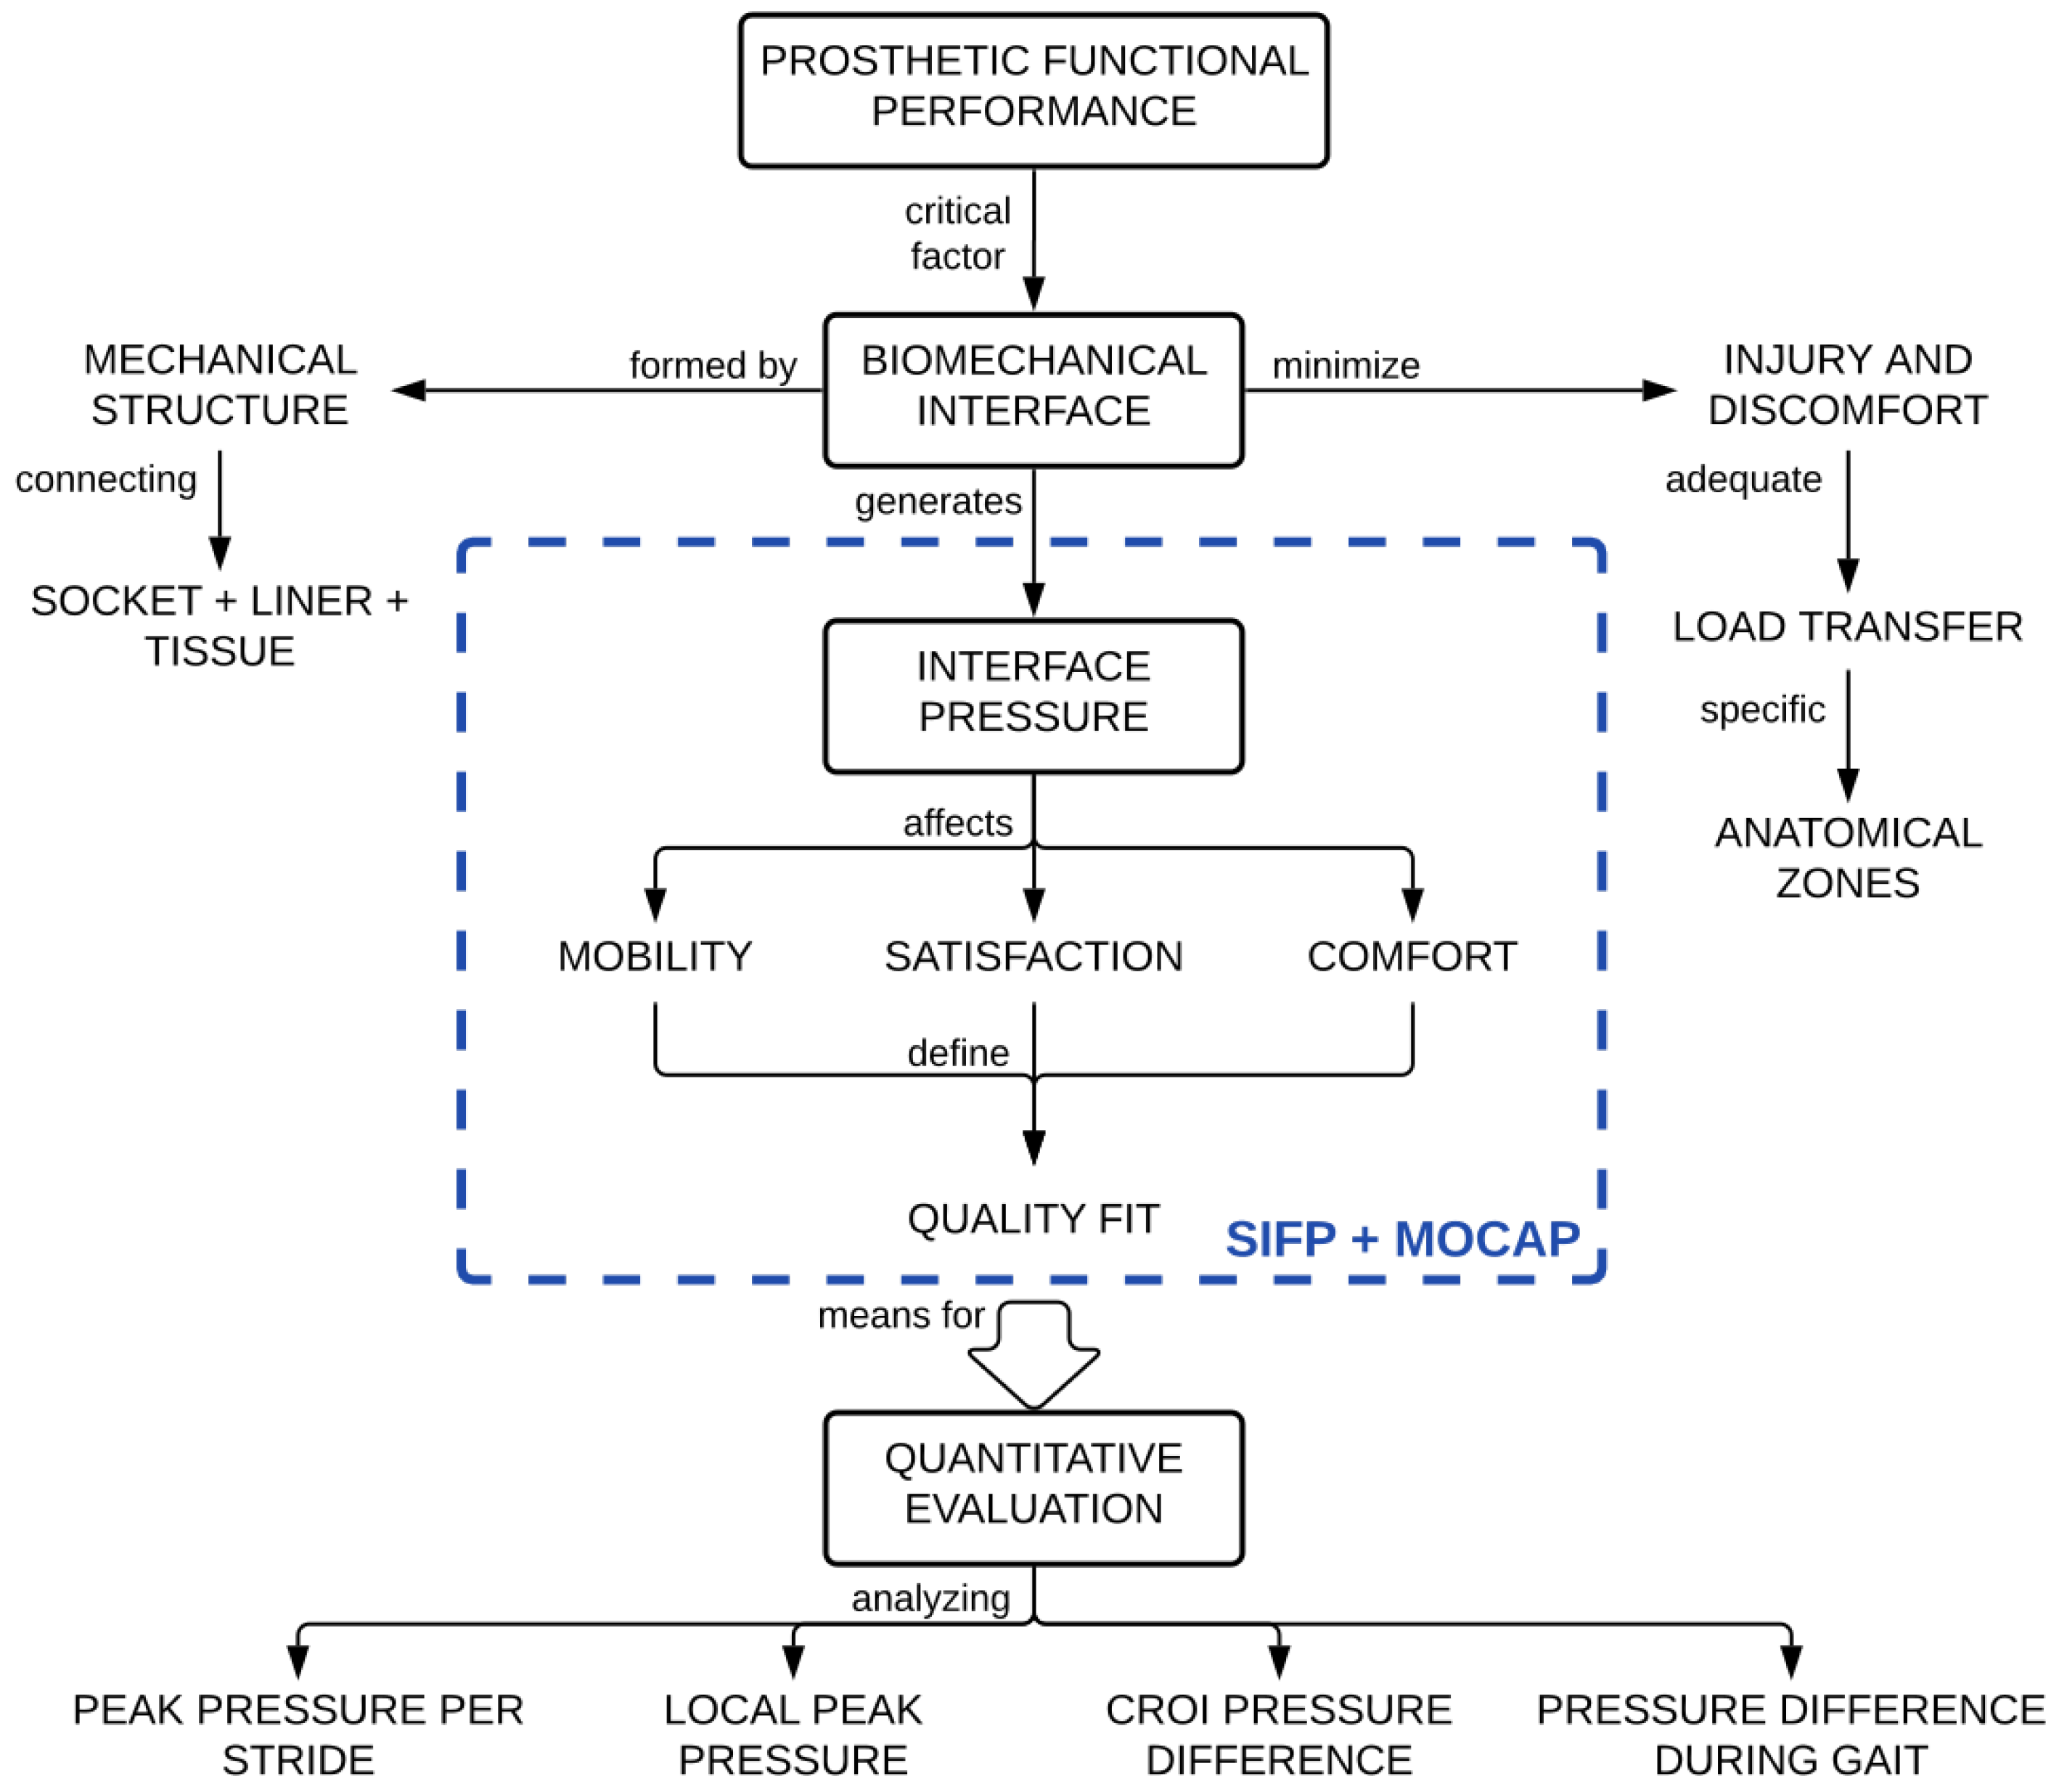

:1. Introduction

The Gait Cycle on the Amputee and the Residuum

- To compare the performance of our socket interface pressure (SIFP) device versus the F-Socket due that both of the them are products able to evaluate the functional performance of prosthesis sockets.

- To evaluate the quality of fit and the functional performance of prosthesis sockets during the gait using the stump/socket pressure distribution of a unilateral amputee by means of a integrated socket interface pressure system. The system comprises a Kinect motion capture system, a portable SIFP device (Bluetooth-enabled), and a MATLAB® code. The system senses the pressure at the CROI of the residual lower limb during the gait and displays pressure graphs and gait graphs in real time.

- To detect via the sensitive range of the 6 sensor array, variations between sockets and pressure values at the CROI which could lead to detect pain points that negatively affect posture and gait of the amputee.

2. Materials and Methods

4. Discussion